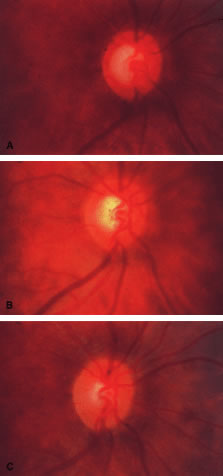

the 10 and 2 o'clock positions of the eye, assumes great significance.  Fig. 9. Indentation gonioscopy. A. The angle appears closed. However, the observer cannot determine whether

this appearance is due to mere contacts between the iris and cornea

or to actual adhesion. B. The goniolens has been pressed against the central cornea, displacing

aqueous into the periphery and showing that the angle is open. C. Indentation gonioscopy displaces the iris posteriorly, showing peripheral

anterior synechiae. (Schwartz LW. Diagnostic evaluation of the patient. In Spaeth GL (ed). Early

Primary Open-Angle Glaucoma: Diagnosis and Management. Boston: Little, Brown & Co, 1979.) Fig. 9. Indentation gonioscopy. A. The angle appears closed. However, the observer cannot determine whether

this appearance is due to mere contacts between the iris and cornea

or to actual adhesion. B. The goniolens has been pressed against the central cornea, displacing

aqueous into the periphery and showing that the angle is open. C. Indentation gonioscopy displaces the iris posteriorly, showing peripheral

anterior synechiae. (Schwartz LW. Diagnostic evaluation of the patient. In Spaeth GL (ed). Early

Primary Open-Angle Glaucoma: Diagnosis and Management. Boston: Little, Brown & Co, 1979.)